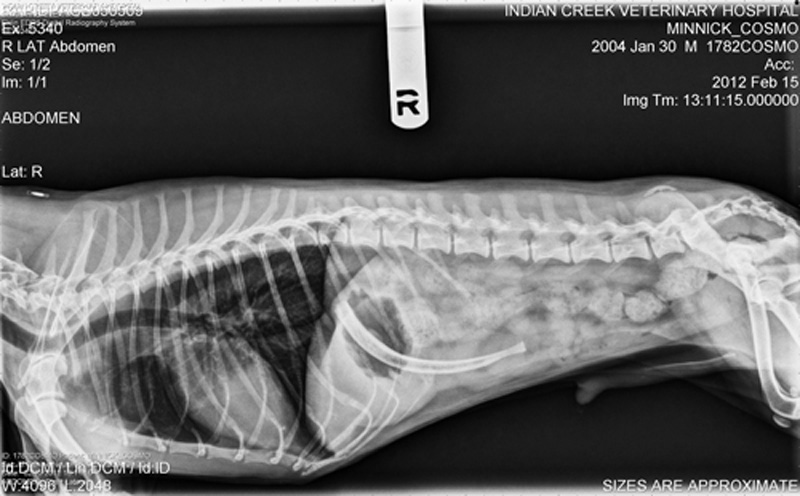

Dog X rays Variety of Radiographs Taken on Dogs